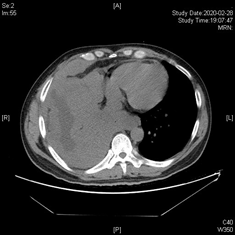

1月后复查胸部CT,肺部病灶及胸膜病灶显著缩小,现患者病情已改善出院。